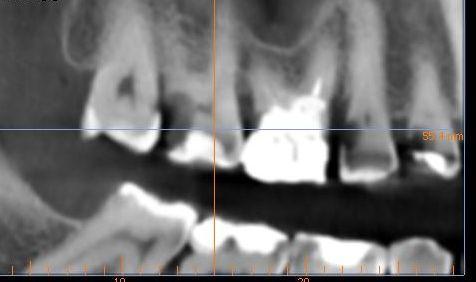

Интересовала в частности развалившаяся 6-ка сверху.

уже давно леченная -перелеченная.

Вердикт -надо кроме нее удалить также и 4 и 5 рядом стоящие - типа киста.

По поводу 6 ки я еще готов удалить так как там похоже невозможно что-то сделать но 4-ка с 5-кой свиду не такие плохие. возможно их перелечить ?

Отскринте нормально снимок: чтобы полностью было видно и корни зубов!

Добрый вечер, может опять не так сделал?

tecom, нормально! А вот на 4 и 5 кисты нет! Но лечить зубов очень много: практически каждый...

Плюс ещё пародонтит в том числе на 4 и 5...